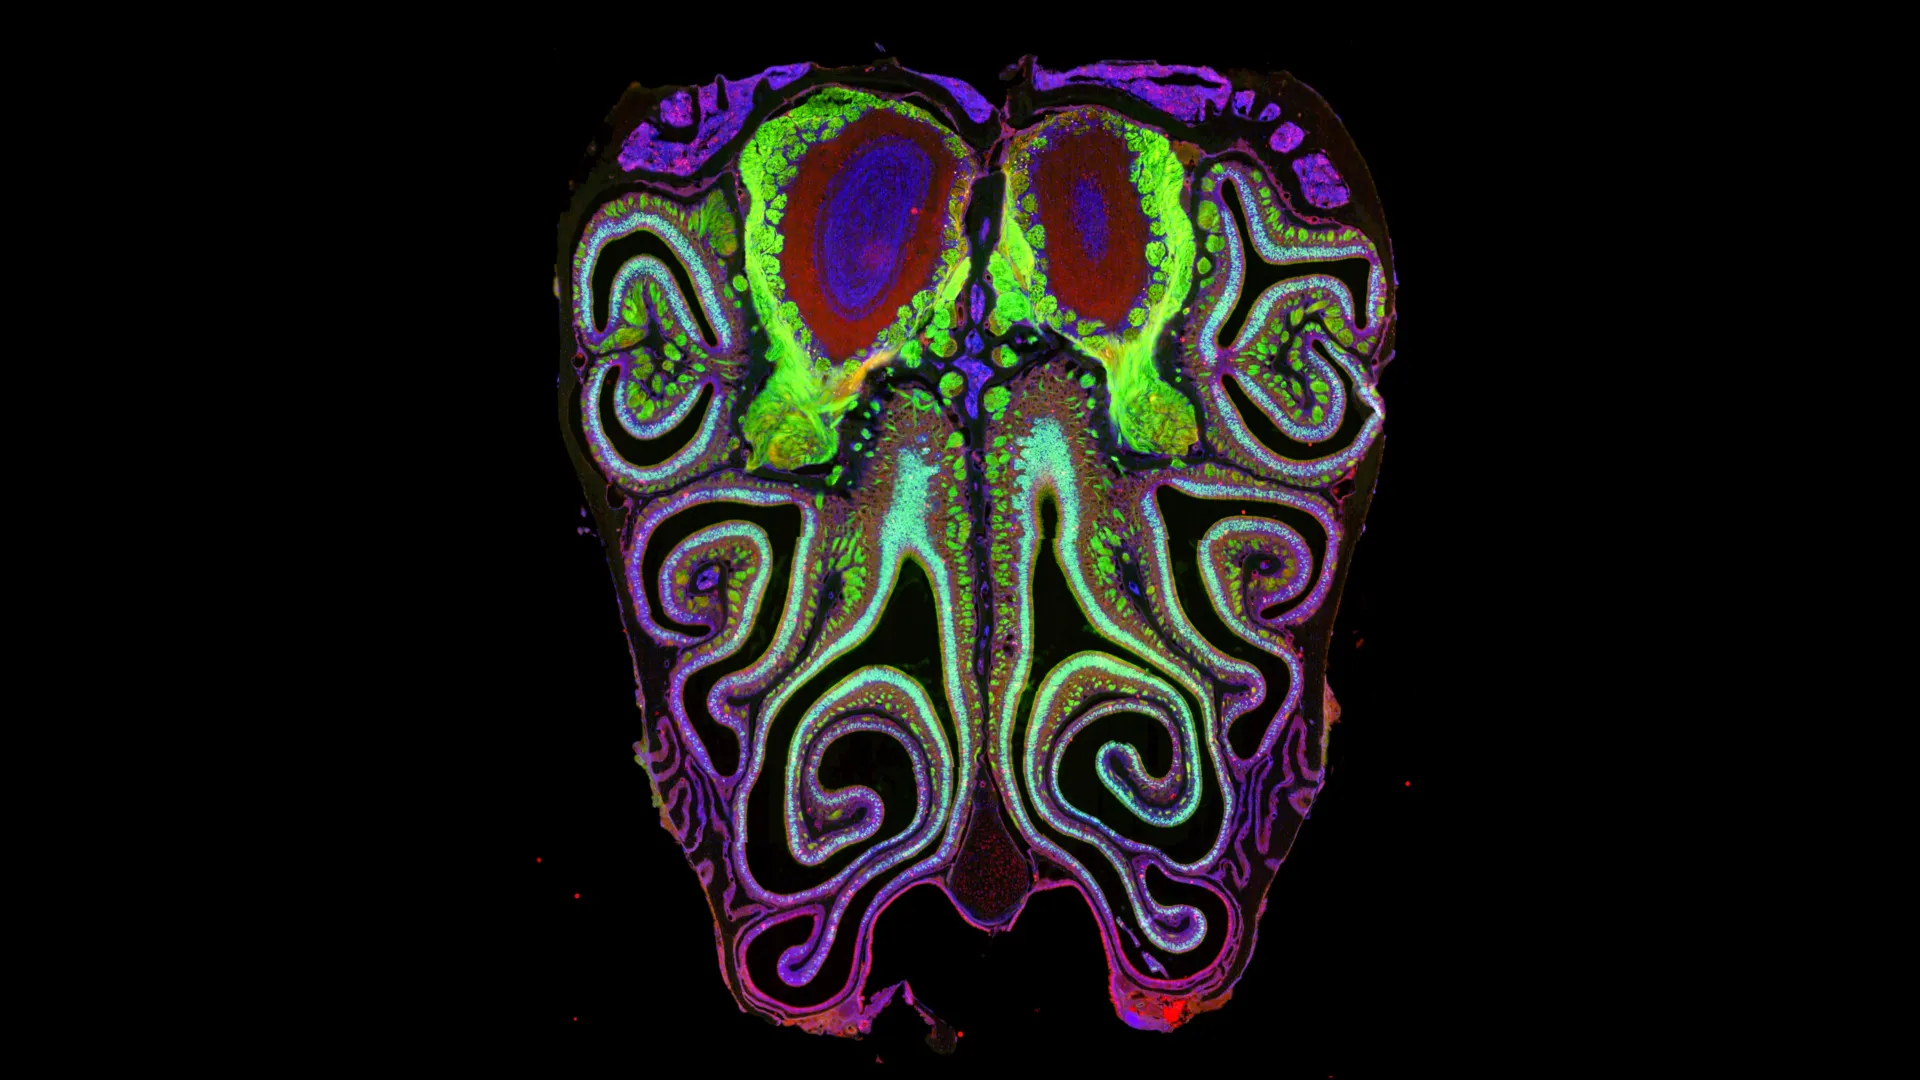

Scientists have finally cracked one of the biggest mysteries in the senses: how smell is organized. By mapping millions of neurons in mice, researchers discover...